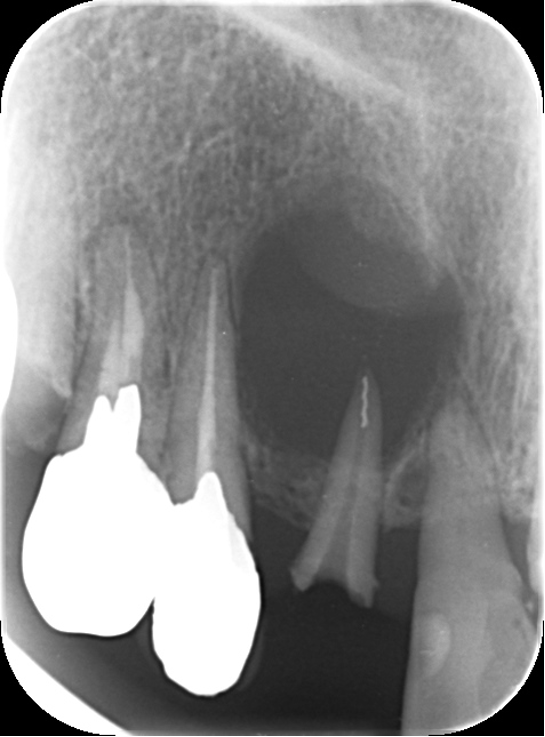

他の歯科医院で治療中です。セカンドオピニオンを希望され来院されました。むし歯が大きかったのでしょう、歯冠は削られてすでにありません。歯根のみ残っています。レントゲンでは歯根の周りに大きな歯根嚢胞が認められます。

歯根嚢胞とは、根管治療がうまくいかなかった場合根管の中の細菌が骨に侵入して骨を溶かし、歯根の周りに袋状に骨が溶けて、膿などの液体がたまる病気です。根管治療がなされていますが、根管の先端に根管治療用の針が折れて残っています。この状態では根管の細菌を死滅させることはできません。